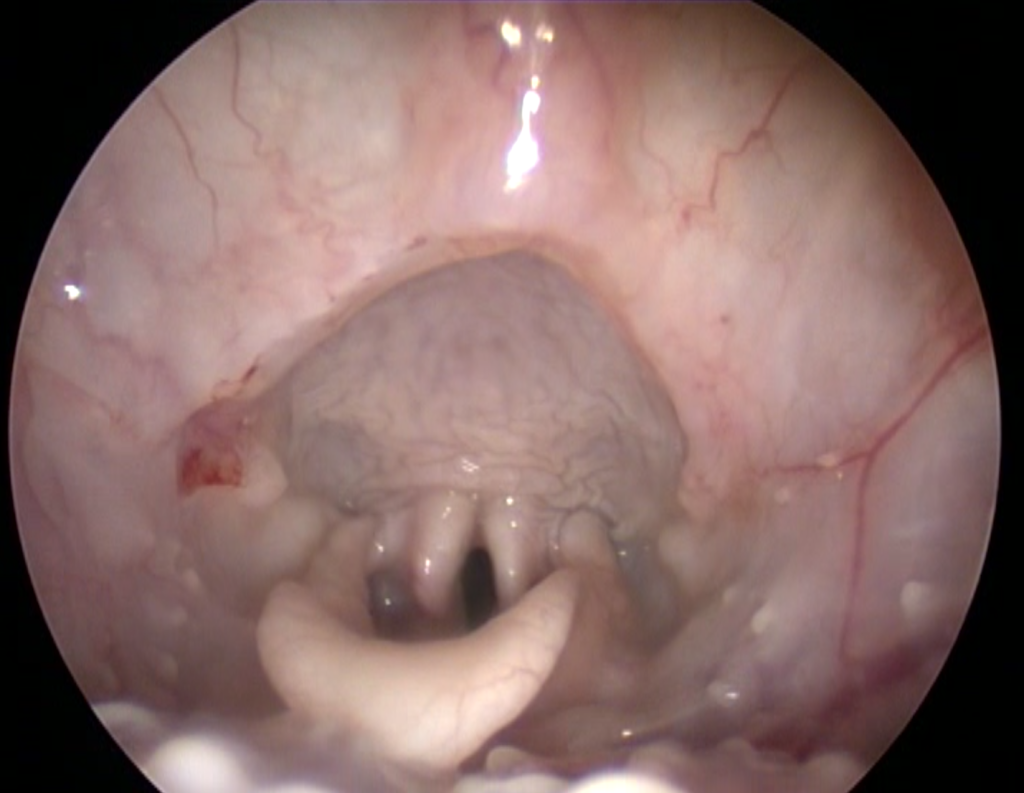

Техника проведения ларингоскопии

Пациент располагается на груди, используется максимально поверхностная седация, голова располагается параллельно туловищу (рис. 2). Позиционирование пациента – очень важный аспект в проведении ларингоскопии. При поднятой голове или широко раскрытой пасти мягкое нёбо смещается каудально, что приводит к некорректной интерпретации результатов исследования.Проводится осмотр гортани и определяется соотношение надгортанника и мягкого нёба. Для корректной оценки необходимо совместить надгортанник с мягким нёбом посредством надавливания пальцем на вентральную часть шеи в проекции корня языка. Пасть при этом должна быть максимально закрыта (рис. 3).

В случае подозрения на наличие ДНФК в процессе проведения ларингоскопии можно наблюдать дорсальное смещение мягкого нёба на вдохе и вентральное – на выдохе.

Гиперплазия мягкого неба не наблюдалась ни у одного из четырех пациентов.